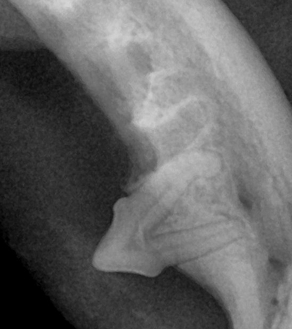

치주염은 진행 정도에 따라 1~4기로 분류되며, 기수에 따라 관리 방법과 치료 방향이 달라집니다.

| 1기 (경도) | 잇몸 가장자리에 염증 발생 | 입 냄새 시작, 이빨 누르면 잇몸 붉어짐 |

| 2기 (중등도) | 염증이 치아 주변까지 확산 | 냄새 심해짐, 딱딱한 사료 꺼림 |

| 3기 (중증) | 치아 지지 조직 파괴 시작 | 이빨 흔들림, 침 흘림 |

| 4기 (중증 이상) | 치아 탈락, 고름, 턱뼈 침범 가능성 | 심한 통증, 입 주변 부음, 만성 염증 |